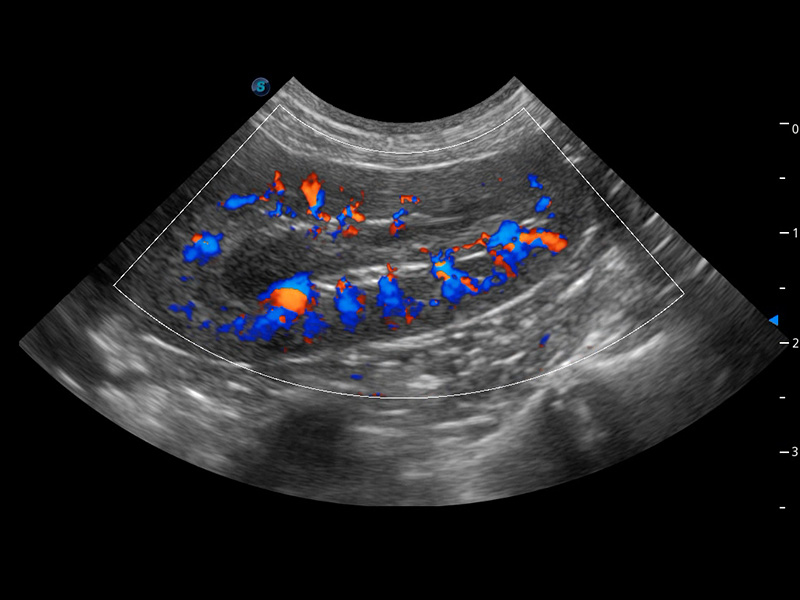

ProPet 60 作为一款高端台式动物超声设备,为动物医生的日常诊断提供了一系列贴合动物临床需求、解决临床实际问题的高级成像功能。凭借全系列高清探头,满足医生对腹部、心脏、生殖、浅表、肌骨等成像的所有需求,切实帮助您提升检查效率,提高诊断信心。

动物是人类最亲密的朋友和最值得信赖的伙伴。DB中国旗舰官方网站也一直致力于探索动物专用的超声影像解决方案。 全新推出的ProPet系列,是DB中国旗舰官方网站在动物超声影像智能化、专业化、精准化的一次跨越式革新。动物不能用言语来表述自己的不适,通过超声影像,ProPet系列搭建了动物医生与不同物种沟通的“桥梁”,为动物医生注入了“治愈之力”。